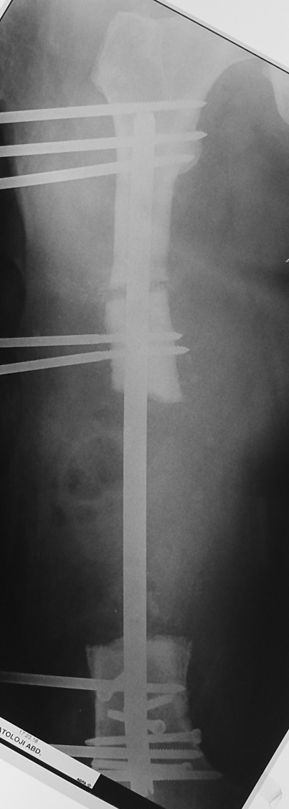

Eksternal fiksatör ile geçen süre (eksternal fiksasyon indeksi), gereken distraksiyon miktarına bağlıdır ve bu süre boyunca bazı komplikasyonlarla karşılaşılabilir. Distraksiyon dönemi sona erdikten sonra, distraksiyon süresinin iki katını aşan konsolidasyon döneminde hastalar eksternal fiksatörü zorlukla tolere edebilirler. Yeterli konsolidasyon sağlanmadan eksternal fiksatör çıkartılırsa ise kırıklar, deformite ve kısalık oluşabilir. Hastanın fiksatör ile birlikte geçirdiği sürenin azaltılması ve böylece hasta konforunun ve aktivite düzeyinin arttırılması için intramedüller çivi üzerinden uzatma yöntemi uygulanmaktadır. Bu yöntemde distraksiyon dönemi sona erdiğinde kemiğin içindeki çivi statik olarak kilitlenmekte ve eksternal fiksatör çıkartılmaktadır. Stabilizasyon intramedüller çivi tarafından sağlandıktan sonra konsolidasyon dönemi gerçekleşmektedir. Bu şekilde hem eksternal fiksatörün uzun süre kalmasından hem de erken çıkartılmasından kaynaklanan komplikasyonların önüne geçilmektedir.

Vaka 1